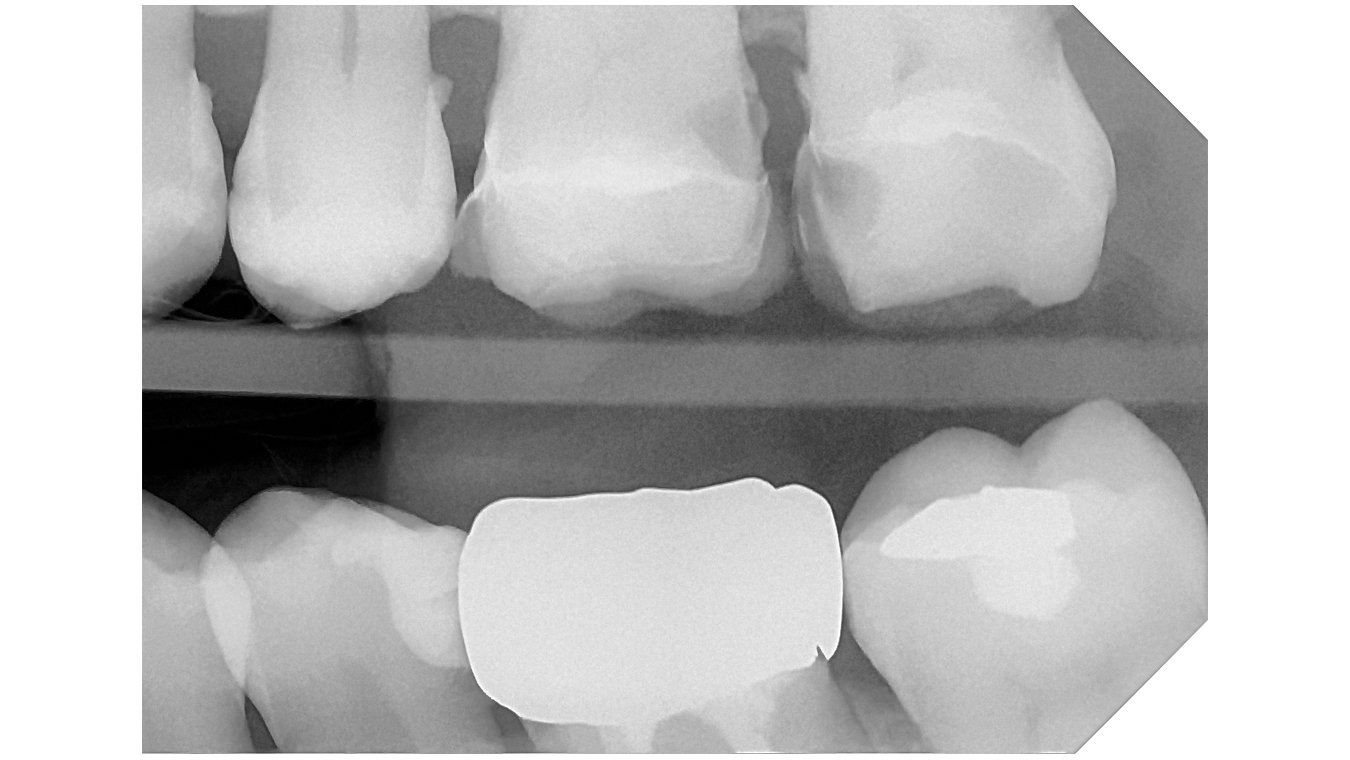

Integrated with the supplied software, the system offers advanced analysis tools and a selection of specific filters to improve image readability in line with clinical requirements:

Default:

High Contrast

High Details

Soft Tissue Preserving

Caries Revealing